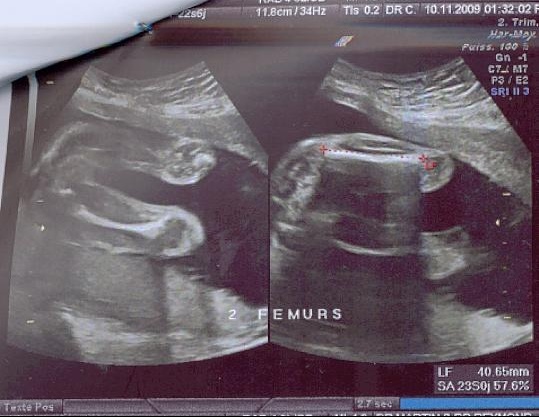

Echographie Des 5 Mois De Grossesse 23 Sa Ou 21 Sg Premiere Grossesse